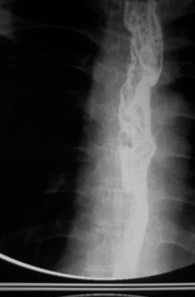

女,51岁,以“进行性吞咽困难1年”为主诉于2007年2月19日入院。钡餐造影、胃镜示食管上段占位性病变,确诊为食道鳞癌(图1),拒绝手术,行放疗+今又生治疗。食道镜下瘤内注射今又生,1×1012VP/次/周×6,放疗在今又生注射3 d后开始,采用常规分割三野等中心照射,剂量65cGY。治疗结束后4周,食管X线、胸部CT显示肿瘤完全消退(图4-5)。

放疗40GY+今又生4支后